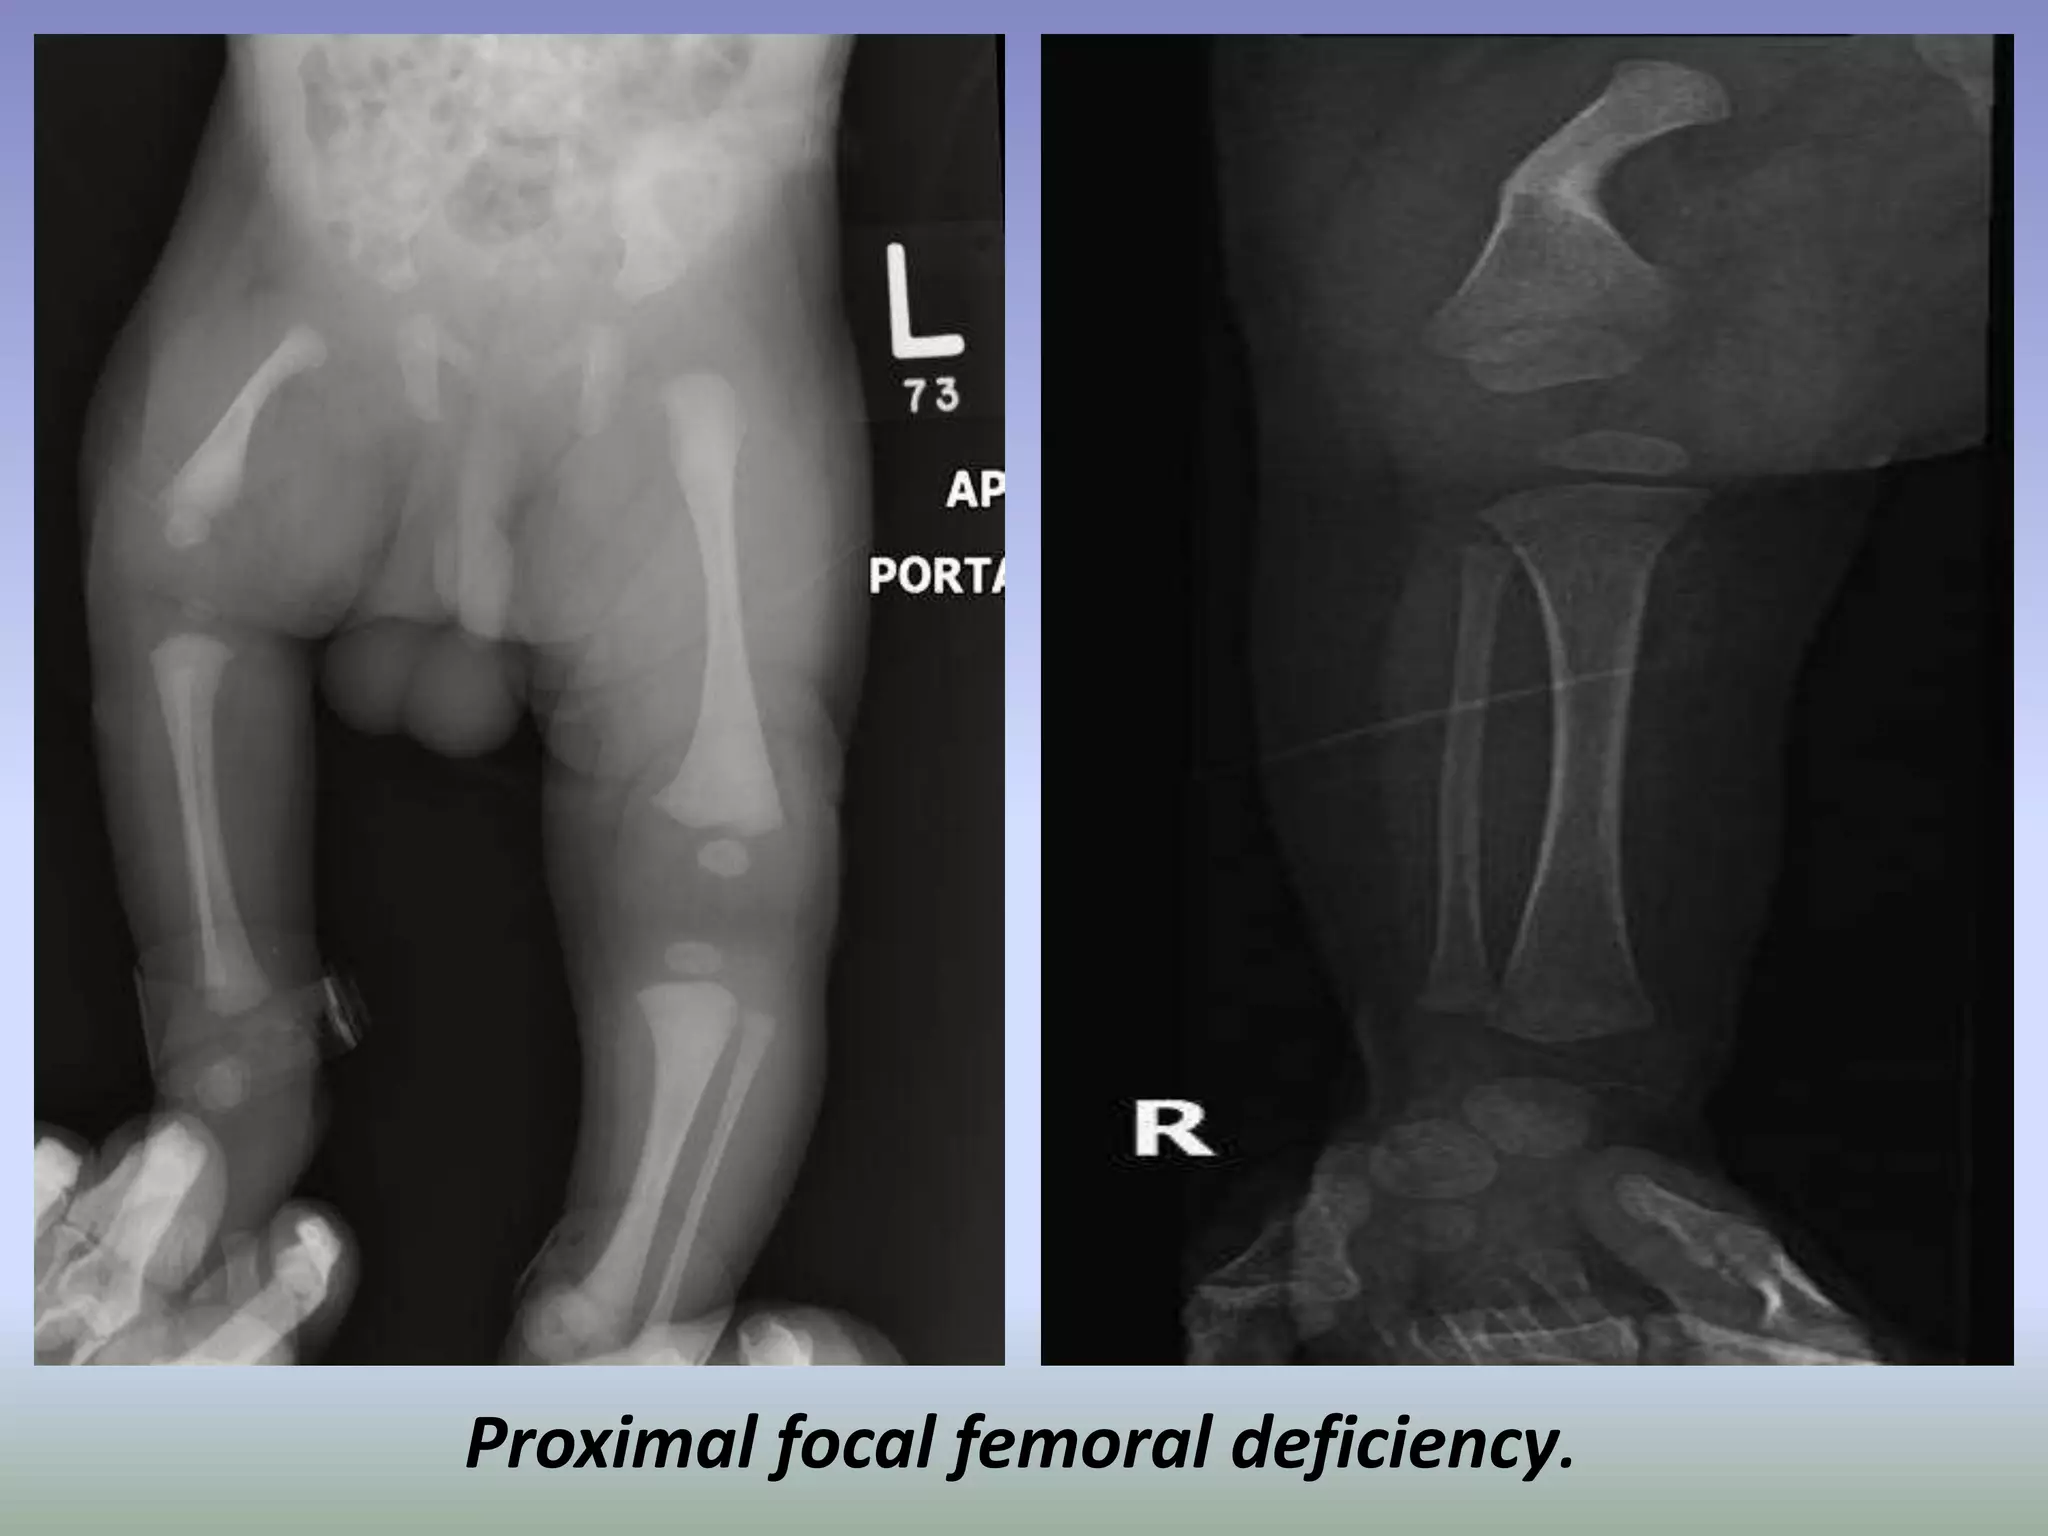

Proximal femoral focal deficiency (PFFD) is a rare, non-hereditary

birth defect that affects the pelvis, particularly the hip bone, and the

proximal femur. The disorder may affect one side or both, with the hip

being deformed and the leg shortened.

It is commonly linked with the absence or shortening of a leg bone (fibular

hemimelia) and the absence of a kneecap. Other linked birth defects

include the dislocation or instability of the joint between the femur and

the kneecap, a shortened tibia or fibula, and foot deformities.

Classifications:

There are typically four classes (or types) of PFFD, ranging from class A to

class D, as detailed by Aitken

Pathology:

The etiology of this disorder is uncertain. The diagnosis and classification

have been based mainly on plain film findings. This method does not

permit definite classification during the 1st year of life.

Associations:

asbent patella.

Proximal focal femoral deficiency.